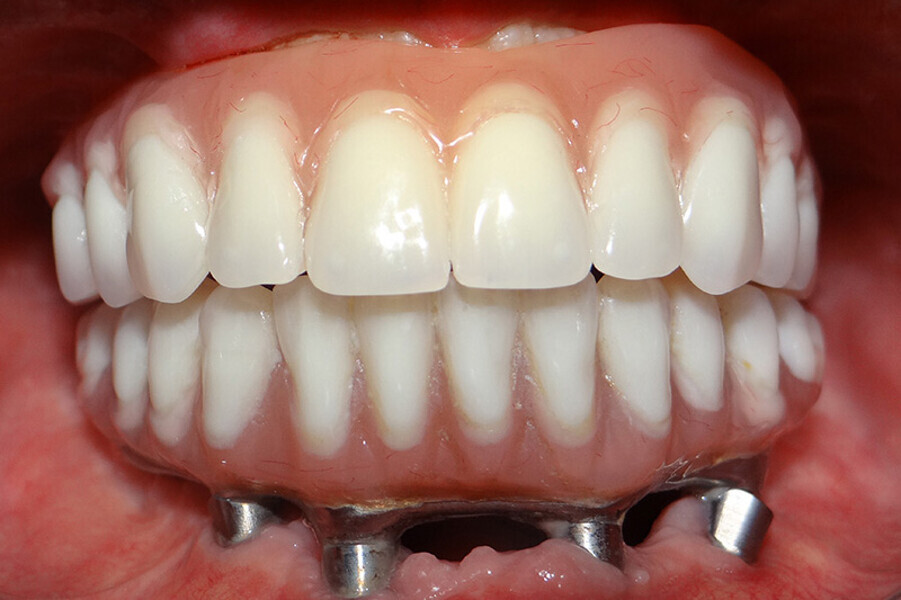

Fig. 6. Prótesis Híbrida inmediata y radiografía control con 6 años post-operatorio